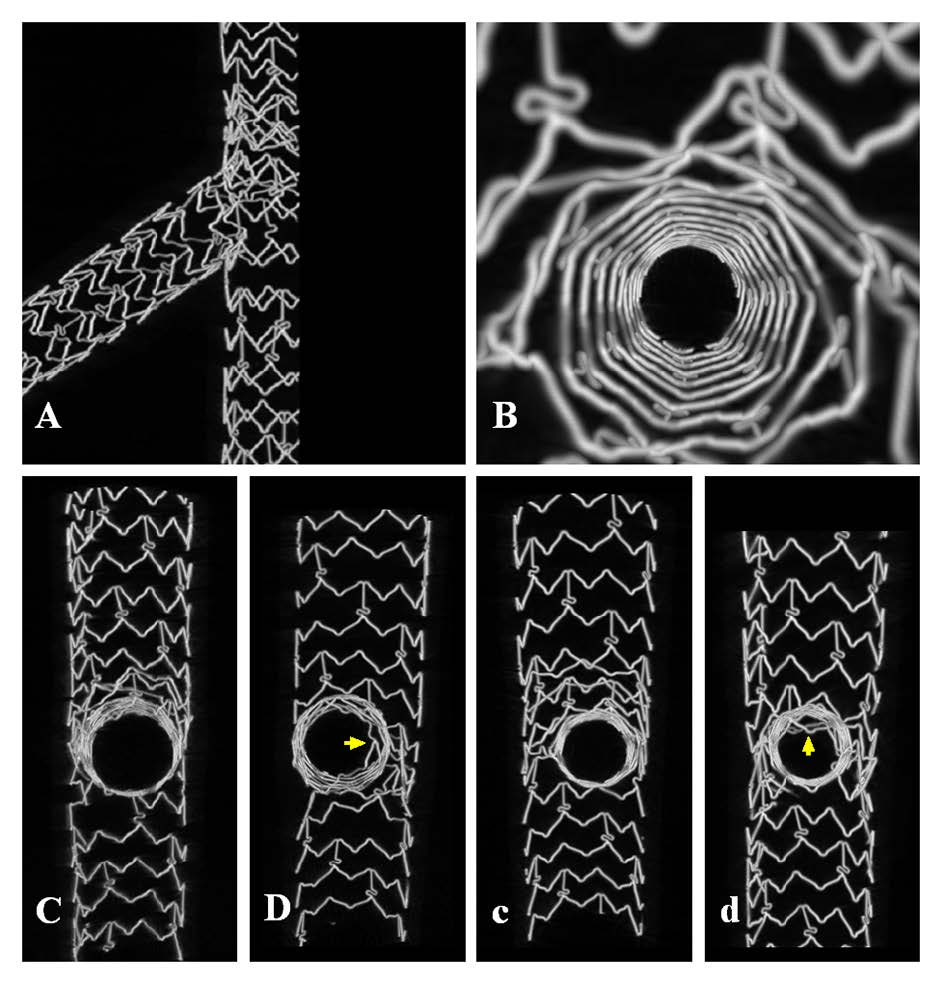

The importance of mandatory POT in provisional stenting technique.

#RadialFirst#Cardiotwitter#bifurcations pic.twitter.com/gMKMuNcgGi

"Double kissing mini-culotte versus mini-culotte stenting: insights from micro-computed tomographic imaging of bench testing" by Fudong Hu et al.

#EAPCI http://bit.ly/2rxIrLU@EuroInterventio@PCRonline@escardio#Bifurcations pic.twitter.com/e47yndRqEU